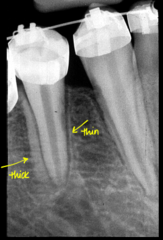

Ortho bands and brackets

Front

Back